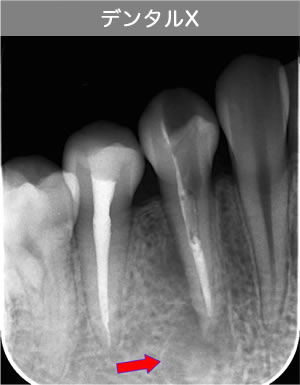

CT画像を見ると根管が2本あることが分かりました。(レントゲンだけでは分かりませんでした。)

| 治療説明 | 右下第2小臼歯、他院で根管治療した後に頬側根尖部から排膿があます。X線CT画像では、根管が2本あり、そのうち舌側が根管充填されていませんでした。顕微鏡下で2根管とも根管充填処置を行い、4ヶ月で、X線透過像は消失しました。 |

|---|---|

| 治療期間 | 6〜24ヶ月 |

| 治療費用 | 150,000〜300,000円 |

| 治療に伴うリスク | 根管内からの治療で根尖病巣が治らない場合は、外科的に根尖病巣を除去する必要があります。 再根管治療を繰り返す場合、歯根の厚みが薄くなり、歯根破折のリスクが高まります。 |

頬側骨壁の根尖部まで無くなっています。

MTA根充後11ヶ月で透過像が消失し、根尖部が正常化しました。

頬側骨の喪失が見られましたが17ヶ月で回復しました。

頬側骨の回復が確認できます。

| 治療説明 | 左下第一小臼歯の頬側根尖部からの排膿、痛みはないそうです。X線画像では根尖部に透過像を認められます。 頬側の骨も失われており、歯髄が死んだことが原因と考えられます。修復物を除去後根管治療を行い、根管充填後、透過像は消失、頬側骨も再生されていました。 |

|---|---|

| 治療期間 | 6〜24ヶ月 |

| 治療費用 | 150,000〜300,000円 |

| 治療に伴うリスク | 根管内からの治療で根尖病巣が治らない場合は、外科的に根尖病巣を除去する必要があります。 再根管治療を繰り返す場合、歯根の厚みが薄くなり、歯根破折のリスクが高まります。 |